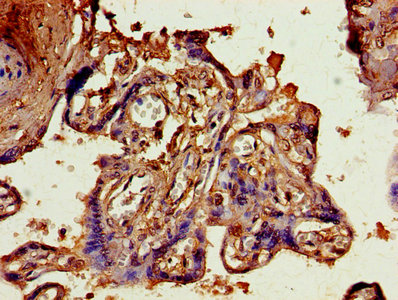

IHC image of CSB-PA05749A0Rb diluted at 1:800 and staining in paraffin-embedded human placenta tissue performed on a Leica BondTM system. After dewaxing and hydration, antigen retrieval was mediated by high pressure in a citrate buffer (pH 6.0). Section was blocked with 10% normal goat serum 30min at RT. Then primary antibody (1% BSA) was incubated at 4°C overnight. The primary is detected by a biotinylated secondary antibody and visualized using an HRP conjugated SP system.

-

IHC image of CSB-PA05749A0Rb diluted at 1:800 and staining in paraffin-embedded human kidney tissue performed on a Leica BondTM system. After dewaxing and hydration, antigen retrieval was mediated by high pressure in a citrate buffer (pH 6.0). Section was blocked with 10% normal goat serum 30min at RT. Then primary antibody (1% BSA) was incubated at 4°C overnight. The primary is detected by a biotinylated secondary antibody and visualized using an HRP conjugated SP system.